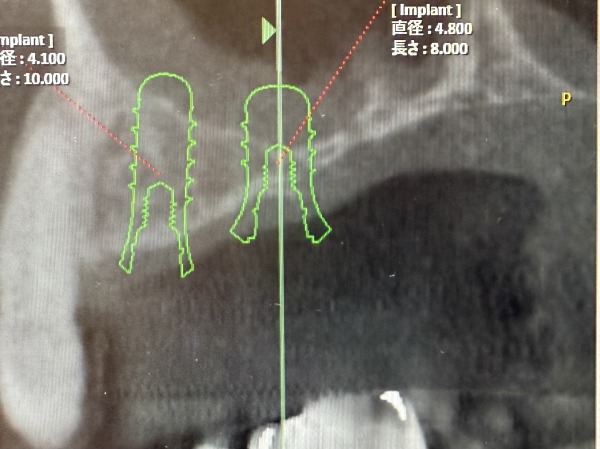

サイナスリフトを行い6ヶ月ほど経過した時点で、CTを撮影しインプラントが問題なく入れられることを確認しました。十分な骨の中にインプラントが埋め込まれているのが分かるかと思います。